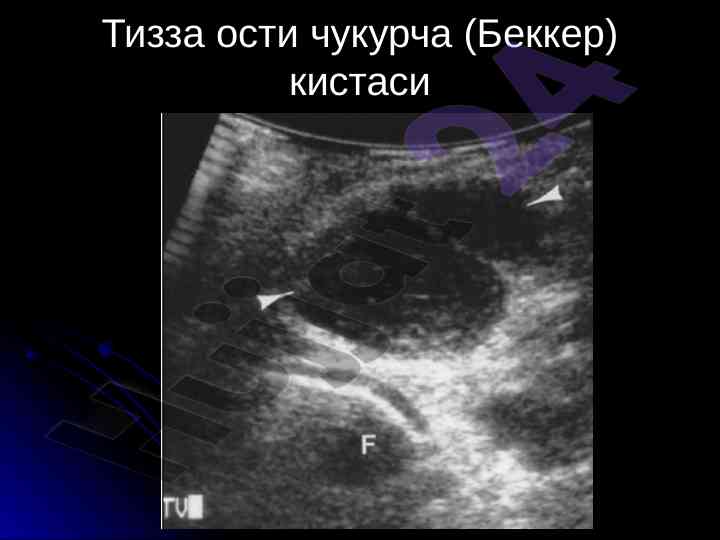

Ushbu mustaqil ishda tayanch-harakat tizimi kasalliklarining nur tashxisi va rentgenografiya orqali suyak minerallanishi holatlari o'rganilgan. Suyak va yumshoq to'qimalar haqida muhim ma'lumotlar taqdim etilgan.